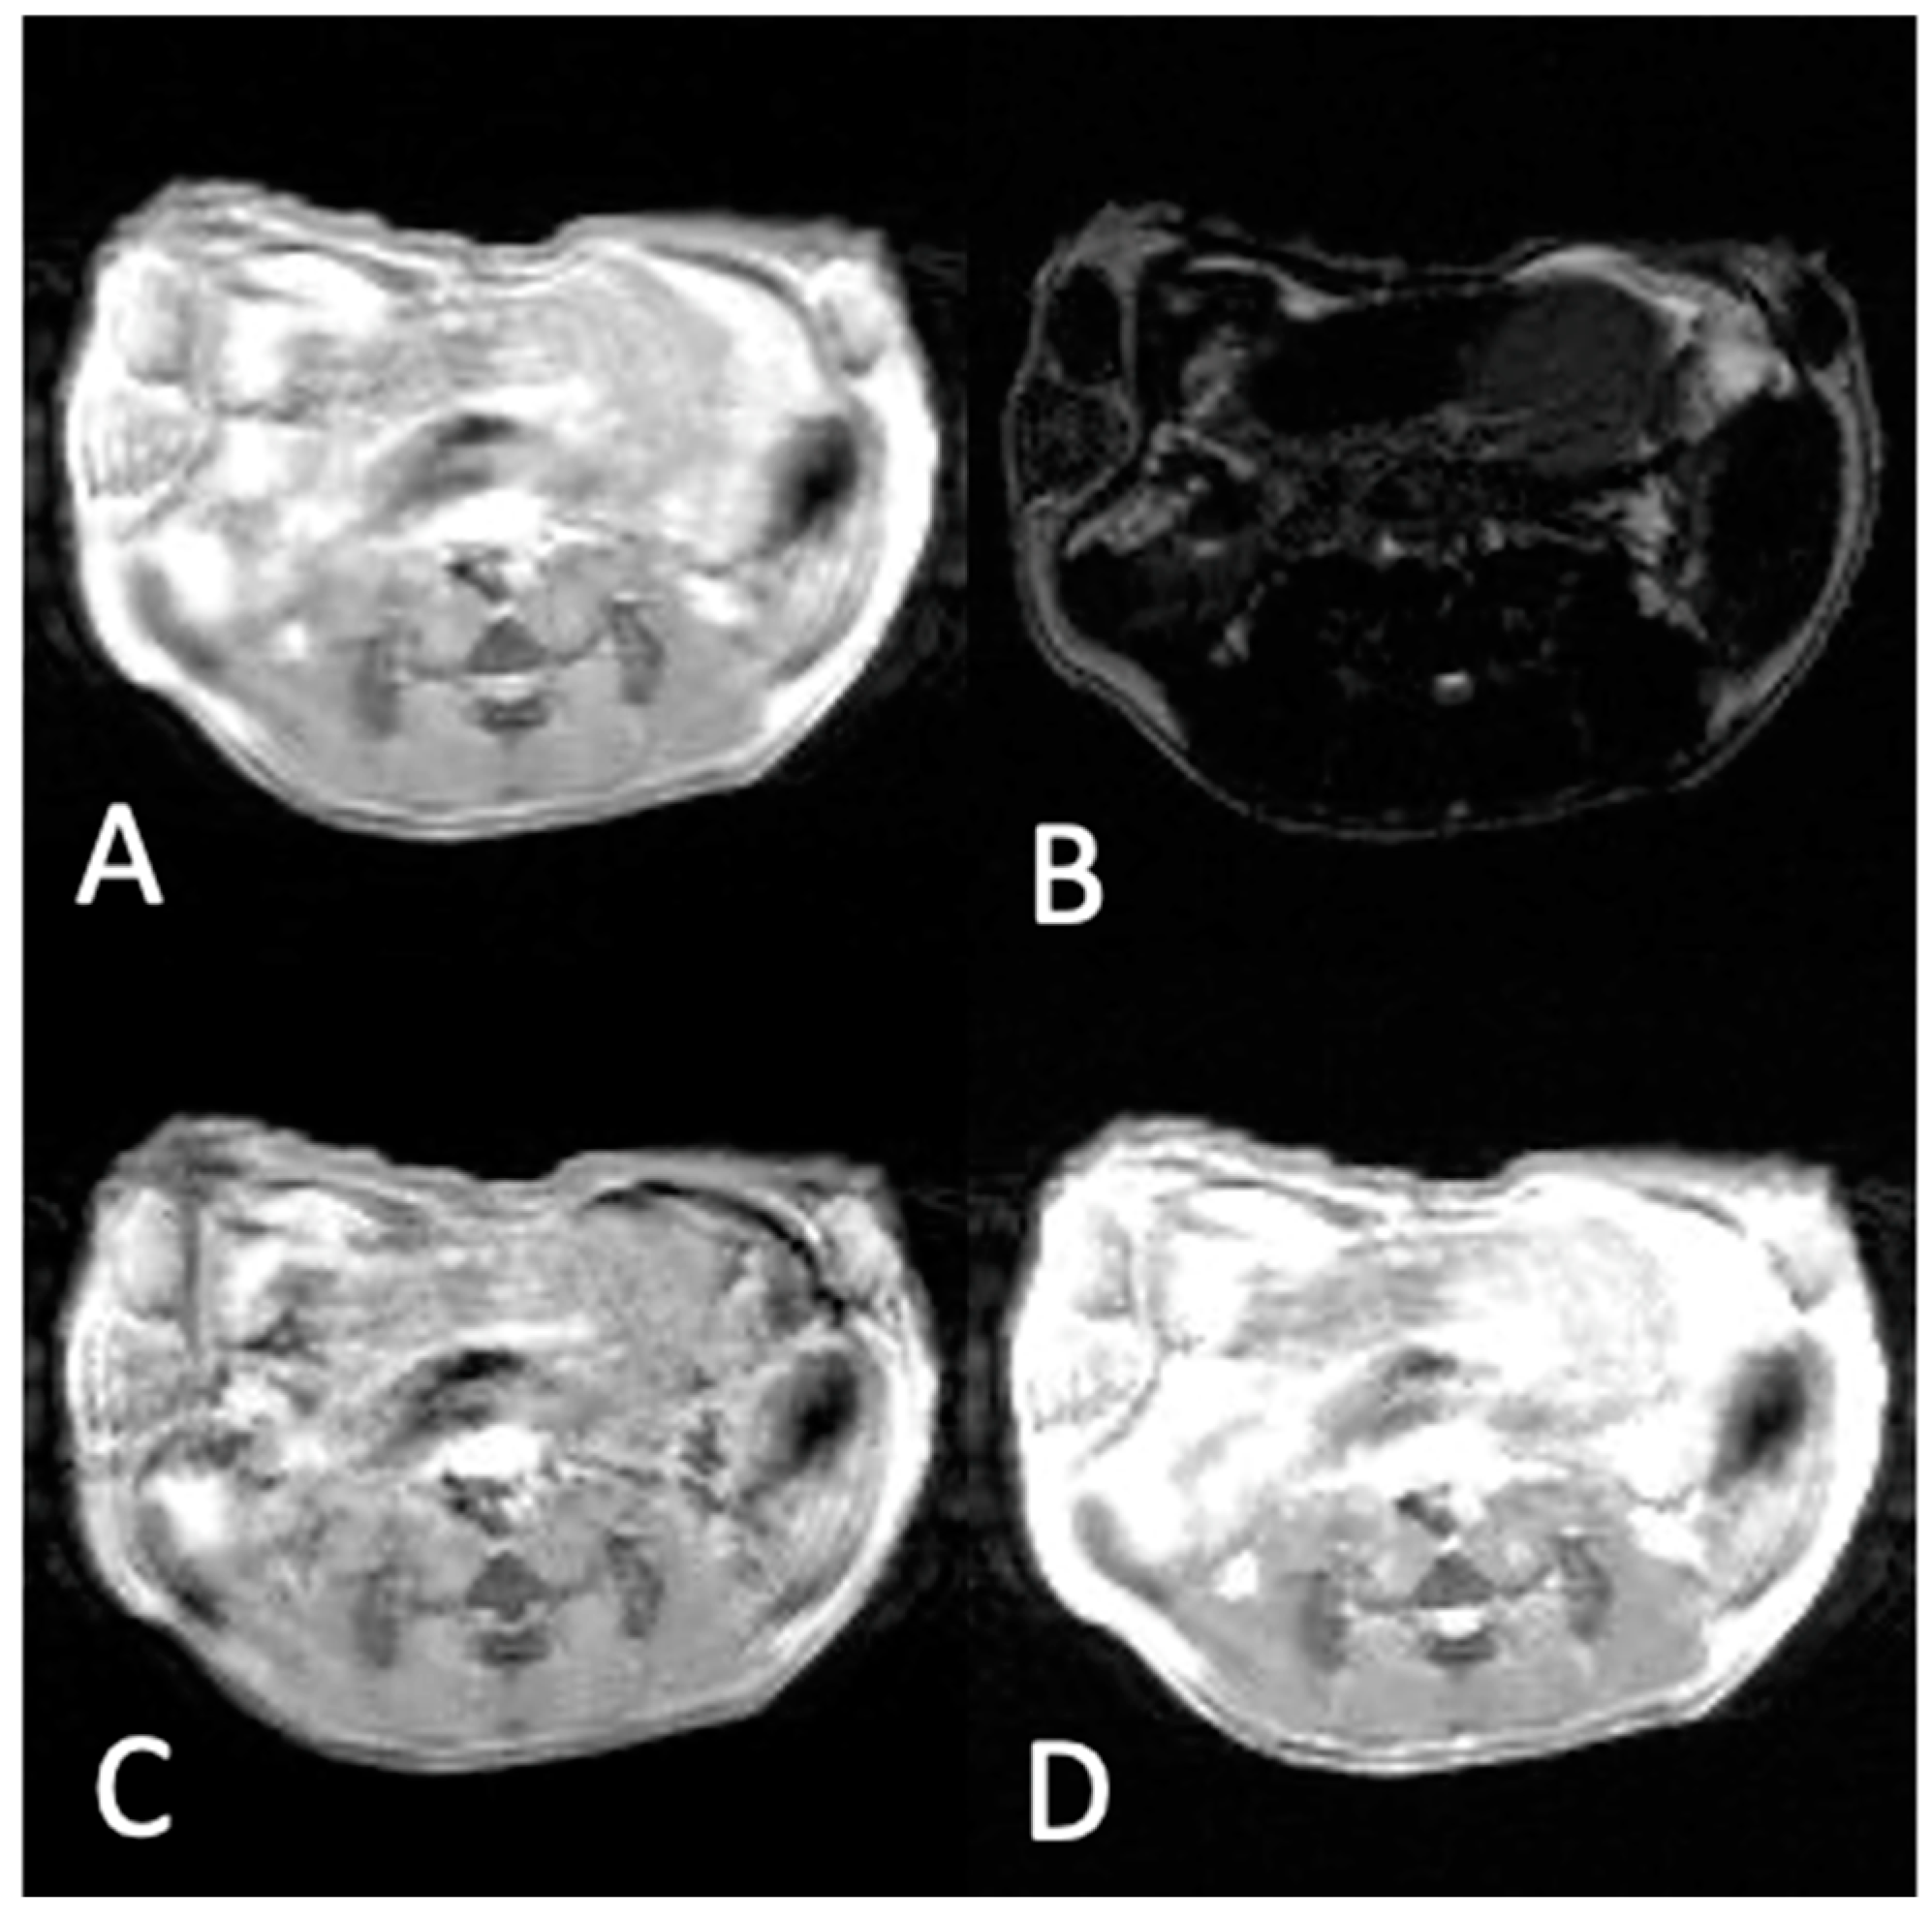

2.4. In Vivo MRI Experiments

2.5. MR Imaging Parameters

3.2. In Vivo Experiments